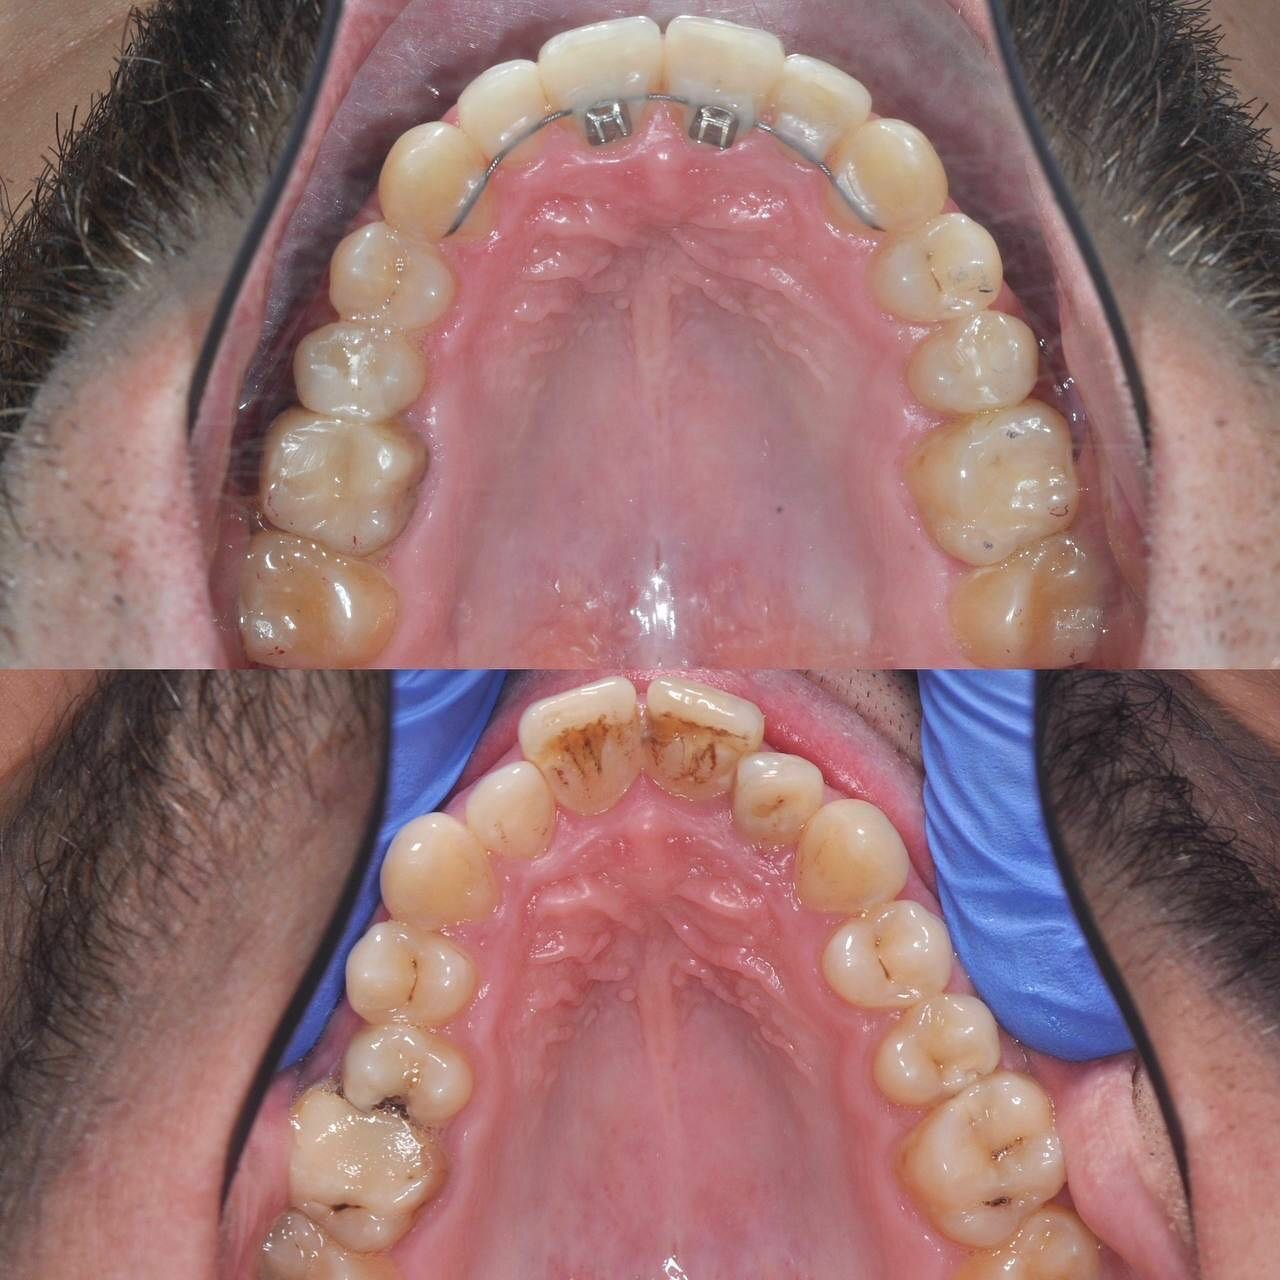

Клиника предоставляет услуги по всем основным направлениям стоматологии, включая общую стоматологию, ортодонтию, хирургическую и эстетическую стоматологию, а также детскую стоматологию. Среди дополнительных услуг: лечение кариеса, пломбирование, удаление зубов, имплантация, протезирование, отбеливание, установка виниров и брекетов, лечение десен и каналов, рентгенография, челюстно-лицевая хирургия и френулопластика.

- ортодонтия

- брекеты

Записывался на консультацию и дальнейшую установку брекетов для исправления прикуса. Впечатления на данный момент только положительные. Работа аккуратная, отношение вежливое, дополнительных услуг не навязывали.